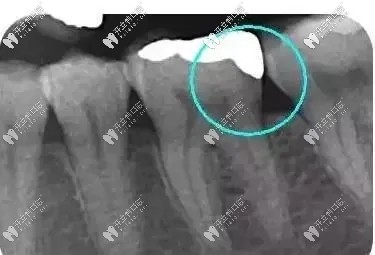

從下面這張X線中可以看出,嵌體遠(yuǎn)中邊緣沒(méi)有懸突,與牙體邊緣密合相接。

牙齒嵌體拍片圖示